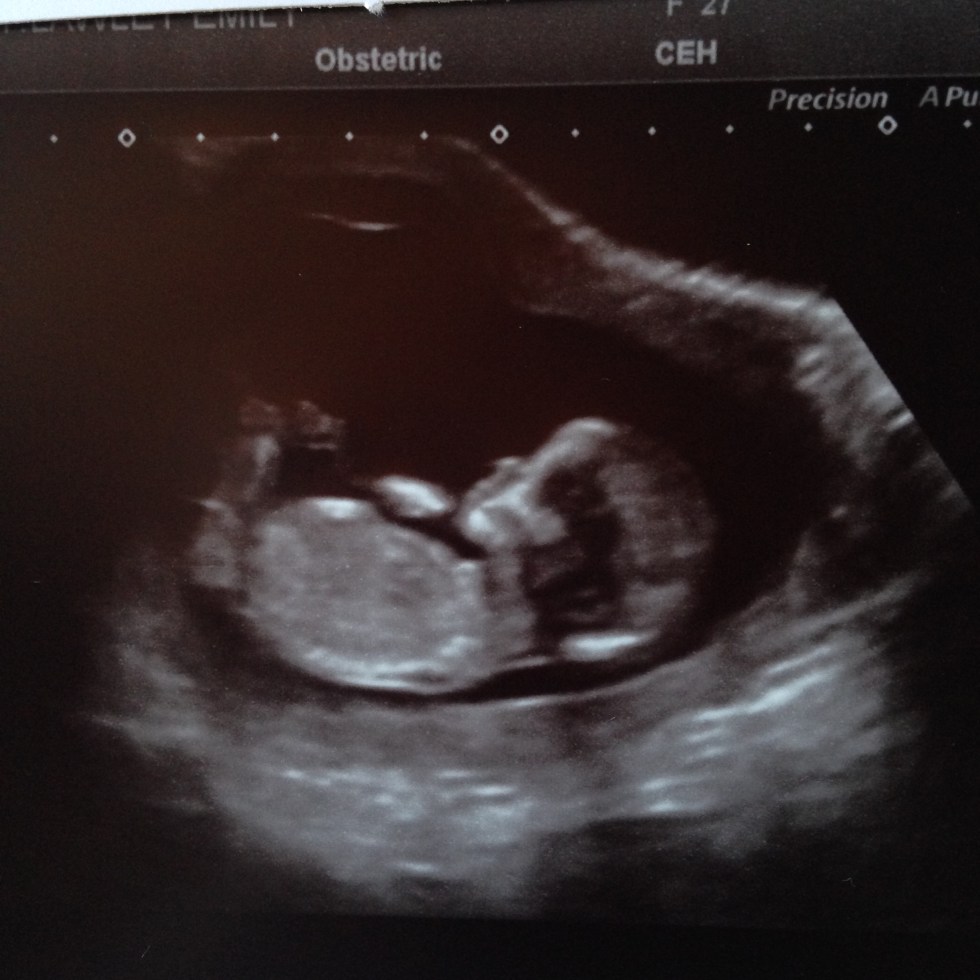

My 12 week scan

Scan day!